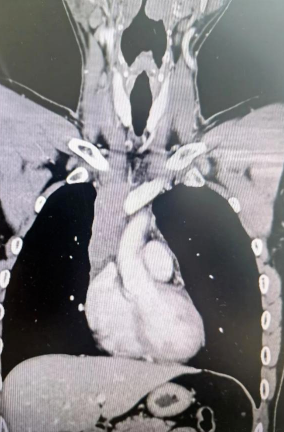

經(jīng)檢查發(fā)現(xiàn)患者前上縱隔腫瘤已經(jīng)完全侵犯了我們?nèi)梭w最主要的大靜脈之一——上腔靜脈,導(dǎo)致上腔靜脈回流嚴(yán)重受阻并導(dǎo)致由上腔靜脈起至左側(cè)無名靜脈、右側(cè)鎖骨下靜脈、右側(cè)頸內(nèi)靜脈等多根自上往下回流的靜脈阻塞,從而形成了廣泛的栓子,牢牢堵住了要流回心臟的血流,只能靠別的一些側(cè)支循環(huán)超負(fù)荷的工作,這也就是為什么孫先生脖子甚至是頭都明顯腫起來的原因。

4月30日,麻醉完成后,縱劈胸骨顯露右上縱隔腫瘤,發(fā)現(xiàn)腫瘤侵入上腔靜脈起始部,右鎖骨下靜脈及右頸內(nèi)靜脈血栓形成并向遠(yuǎn)端延伸。劉志主任團(tuán)隊將切口向右頸部延長,顯露右側(cè)頸內(nèi)靜脈至下頜角水平。張金洲副院長團(tuán)隊經(jīng)股動靜脈和左無名靜脈建立體外循環(huán)。在阻斷左無名靜脈遠(yuǎn)端后,李文海副院長團(tuán)隊完整切除縱隔腫瘤及部分上腔靜脈、左無名靜脈、右鎖骨下靜脈和右頸內(nèi)靜脈切除。張金洲副院長團(tuán)隊實施了無名靜脈近端、右鎖骨下靜脈和右頸內(nèi)靜脈內(nèi)血栓取出術(shù),并完成了左無名靜脈、右頸內(nèi)靜脈和右鎖骨下靜脈的人工血管置換手術(shù)。歷時6小時,三個外科團(tuán)隊在麻醉科柴偉主任團(tuán)隊、體外循環(huán)團(tuán)隊以及食管超聲和手術(shù)室協(xié)作下,手術(shù)獲得成功。

術(shù)后患者經(jīng)過心外監(jiān)護(hù)室和胸外監(jiān)護(hù)室的接力治療,目前患者恢復(fù)順利,顏面部腫消失。復(fù)查增強(qiáng)CT三條人工血管通暢。